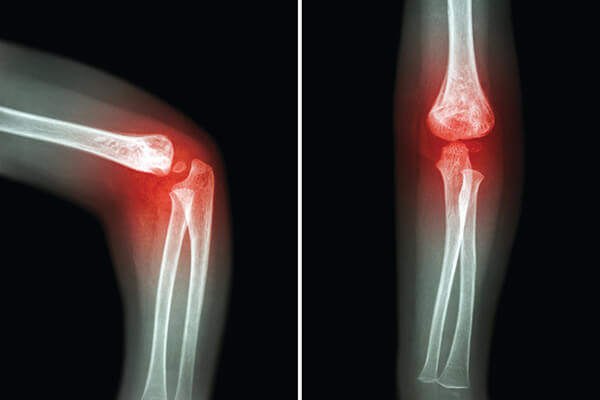

Σε ότι αφορά την Αρθροσκοπική χειρουργική του Αγκώνος, με την εφαρμογή 2-3 πολύ μικρών τομών (5-7 χιλιοστών, η κάθε μία), εισάγεται μία κάμερα με ισχυρό φωτισμό μέσα στην άρθρωση, επιτρέποντας στον χειρουργό να έχει, υπό μεγέθυνση, πλήρη εκτίμηση της κατάστασης της άρθρωσης στην οθόνη, και με την χρήση ειδικά σχεδιασμένων μικρών εργαλείων, να αποκαθιστά την βλάβη.

Αρθροσκοπικά μπορούμε να αποκαταστήσουμε στην άρθρωση του αγκώνα τα παρακάτω προβλήματα:

- Αφαίρεση ελεύθερων σωμάτων

- Χόνδρινες βλάβες

- Δυσκαμψία αγκώνος - Συμφυσιόλυση

- Διαχωριστική οστεοχονδρίτιδα

- Σηπτική αρθρίτιδα